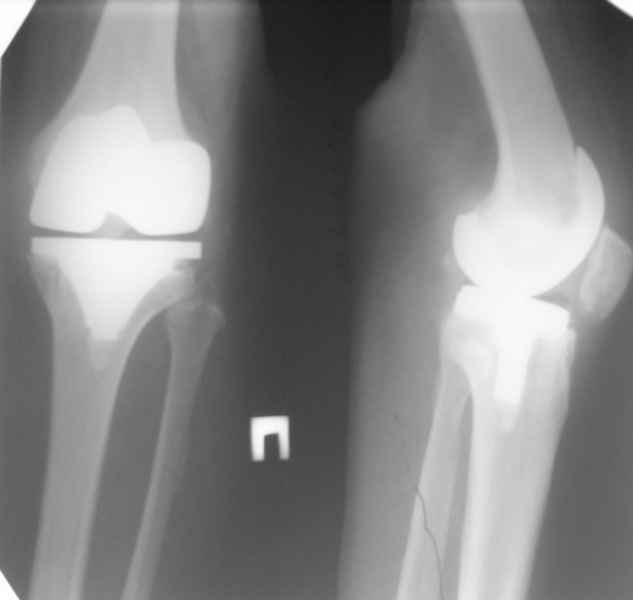

13/02/07 |  25/07/07 |  дек. 07 |  25/06/08 |  14/01/09 | Через 1 месяц после операции объем движений 90 градусов, через 2 месяца 60, через 3 - 40, через 5 - качательные движения.

В июле 2007 года выполнена ревизия - полости сустава нет. Капсула сустава имеет толщину от 1 до 1.5 см, собственная связка надколенника имеет толщину до 3 см. Сустав заполнен фиброзно-рубцовой тканью. Компоненты стабильны.

Есть вопросы к установке протеза. Скорее всего тибиальное плато было не конца резецировано и в задненаружных отделах осталась ступенька. Это привело к тому, что тибиальный компонент завалился на варус.

Ты мне говорил об этом случае, а теперь я увидел снимки. Для исключения или подтверждения гнойного процесса надо взять обязательно посев. По-моему и бедро шатается. Ревизовать при ислючении гнойно-септических осложнений надо полностью либо CCK комплектом или связанным.

По представленным снимкам (patella infera) и по клиническому описанию у Вашего больного типичный Артрофиброз (Knee Arthrofibrosis) обычное после замены сустава осложнение, характеризуется ограничением движения в суставе за счет образования рубцовой ткани. Такое осложнение встречается и после травм коленного сустава или после восстановительных работ на передней крестообразной связке.